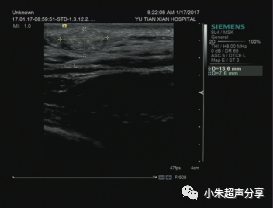

病例1  女 ,5岁,右侧颈部毛母质瘤,

周边可见少量血流信号